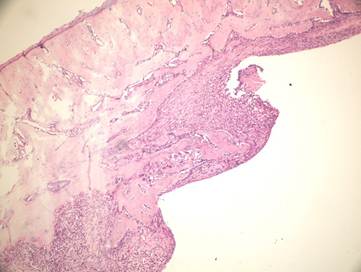

Figure 4

Newly formed bone in group +4°C (H&E x100)

Although there was no statistically significant difference between the group irrigated with 25°C and 4°C saline for new bone formation, latter group had numerous osteoblasts and more prominent osteoblastic rim around the trabeculae of new bone (Figures 4,5). These results indicate that there is no disadvantage to use 25°C saline irrigation, but it may be better to use 4°C saline irrigation for rapid healing.